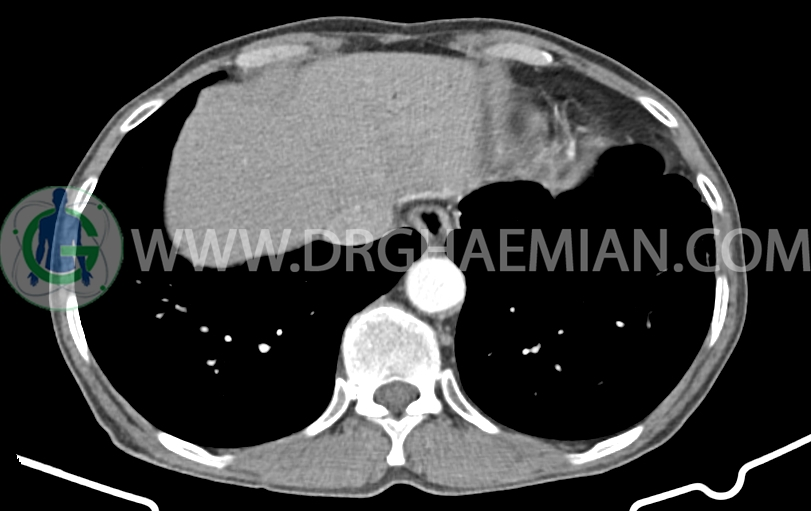

شواهدی استرنوتومی و کاردیومگالی خفیف

لنف نودهای مدیاستینال به حداکثر )جدید نسبت به سی تی اسکن 1401/06/06(

ندول های ground glass سنتری لوبولار پراکنده در دو طرفه همراه با تغیرات برونشکتازی سیستیک در LLL

باند فیبروتیک در لتروبازال LLL

مشهود است.